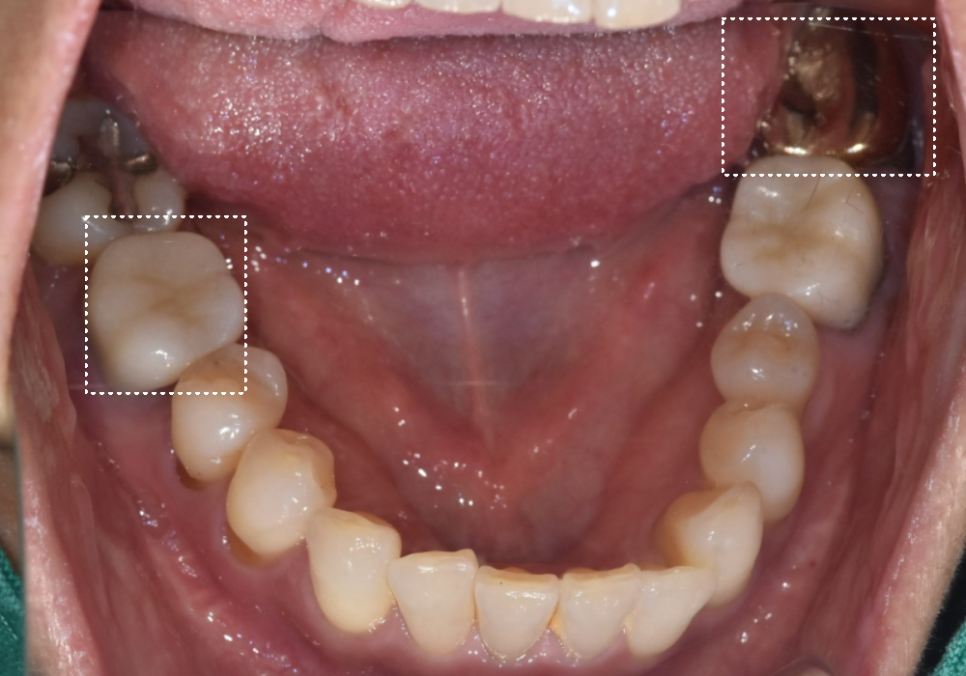

양쪽 아래 어금니가 흔들려

내원하신 환자분 사례

고덕역 임플란트, 뼈이식 꼭 해야 할까?

얼마 전 양쪽 아래 어금니가 흔들린다며

저희 치과를 찾아주신 분이 계셨습니다.

겉으로 보기엔 멀쩡해 보였지만,

방사선 사진을 찍어보니

상태가 생각보다 심각했어요.